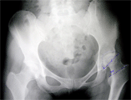

Post

Op

total hip replacement thru minimally invasive single incision

Progress

Patient wih good pain relief and hip motion